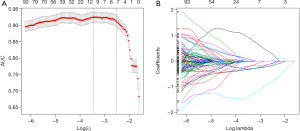

The intraclass and interclass correlation coefficient (ICC) was used to evaluate the consistency of the extracted features, and features with ICC >0.75 were considered to be consistent, reproducible and stable (17). In this step, a total of 8 features with ICC ≤0.75 were deleted, leaving 1,210 features. After that, the least absolute shrinkage and selection operator (LASSO) algorithm was used to screen the stone feature parameters.

Selected stone features

The 1,210 features were screened by 10-fold cross validation, and 8 features with non-zero coefficients were finally obtained, as follows: original_firstorder_10Percentile, log.sigma.1.0.mm.3D_firstorder_90Percentile, log.sigma.2.0.mm.3D_glcm_Imc1, log.sigma.2.0.mm.3D_glcm_InverseVariance, log.sigma.4.0.mm.3D_glcm_InverseVariance, log.sigma.5.0.mm.3D_glcm_Inverse

Variance, wavelet.HLH_glcm_Idn, wavelet.HHL_gldm_DependenceVariance, and wavelet.HHH_firstorder_Median (Figure 4).